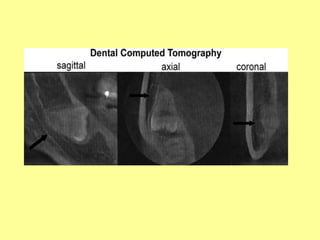

PREVENTION OF NERVE INJURIES

1)Imaging guided operative procedure

• Use of computed tomography to determine

the exact location of M3 and IAC (arrows).

• Multiple orientations (sagittal, axial, coronal)

give exact information to assist the clinician in

decisions regarding planning for partial or

complete M3 removal.